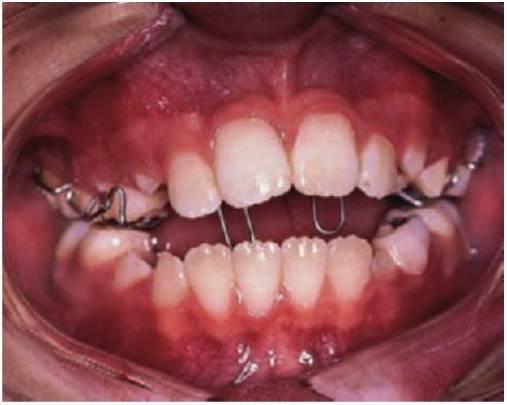

Aparatos fijos

- Los aparatos fijos se pueden utilizar cuando dos o más incisivos están en mordida cruzada.

- Los brackets unen los incisivos con bandas cementadas a los primeros molares permanentes.

- Se utiliza un alambre de arco labial de 0,406 mm con topes de bucle vertical mesiales en los tubos molares. Estos bucles están expandidos para proclinar los incisivos y el alambre redondo permite la inclinación labial de los incisivos para corregir la mordida cruzada.

- En las zonas en las que la mordida cruzada de los incisivos resulte una combinación de inclinación palatina de los incisivos superiores e inclinación labial de los incisivos inferiores, se pueden utilizar aparatos fijos en ambas arcadas en los incisivos y en los primeros molares permanentes.

- Se pueden utilizar elásticos de clase III (que van desde los molares maxilares hasta los caninos mandibulares). Se deben llevar puestos estos elásticos 24 horas al día, excepto para el cepillado de los dientes y sustituirlos cada 3-4 días. Este aparato proporcionará la corrección rápida de la mordida cruzada en un plazo de 6 meses (fig. 11.12).